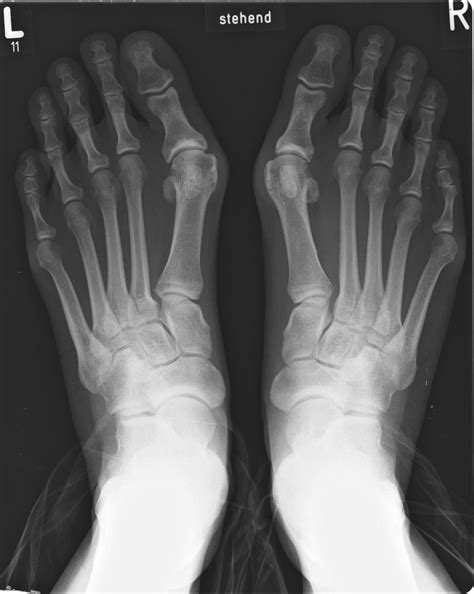

Bunion Surgery – Myths vs Reality - Bunion Surgeon London